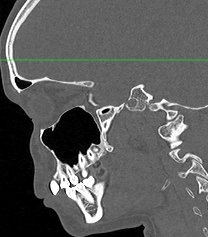

Мультиспиральная компьютерная томография челюстно-лицевой области относится к лучевым методам исследования и включает в себя сканирование верхней и нижней челюстей, зубов, височно-нижнечелюстных суставов, мягкотканных структур ротовой полости. Преимуществами КТ является быстрота, безболезненность и неинвазивность (то есть исследование не требует вмешательства в организм).

В результате сканирования получается серия изображений, которые отображают состояние челюстно-лицевой зоны, особенности анатомического строения и позволяют выявить воспалительные изменения, травматические повреждения, опухолевые образования, аномалии развития. Проявления артроза височно-нижнечелюстных суставов могут создавать неприятные ощущения при жевании. Также зачастую воспалительные изменения придаточных пазух носа связаны с пролабированием зубов верхней челюсти в область альвеолярных бухт верхнечелюстных синусов.

В наших медицинских центрах обследование челюстно-лицевой зоны проводится на современных мультиспиральных компьютерных томографах экспертного класса TOSHIBA AQUILION. 64- и 128-срезовый компьютерные томографы послойно сканируют исследуемую область с шагом от 0,5 мм, получая детальные изображения высокого уровня четкости и контрастности.

С помощью цифровой обработки данных проводится объемная реконструкция и построение 3D-изображений челюстно-лицевой области, что дает возможность визуализировать пространственное соотношение анатомических структур и повышает точность диагностики. При этом возможности аппаратов обеспечивают пониженный уровень дозы облучения для организма человека.